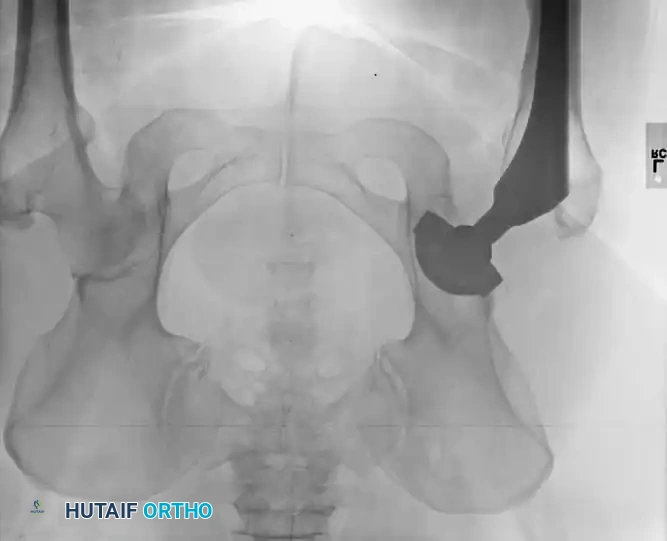

Postoperative heterotopic ossification (HO) varies dramatically in its clinical and radiographic presentation, ranging from a faint, indistinct density seen in the region of the abductors and iliopsoas to complete, debilitating bony ankylosis of the hip joint.

Calcification can typically be visualized radiographically by the third or fourth postoperative week; however, the ectopic bone does not mature fully for 1 to 2 years. The classification system developed by Brooker et al. remains the gold standard for describing the extent of bone formation:

- Grade IV: Complete radiographic bony ankylosis.

The overall prevalence of this complication averages approximately 10% in modern series, though historical data by Riegler and Harris reported occurrences in up to 50% of patients. Fortunately, most patients who develop HO remain asymptomatic. However, restricted range of motion and pain are common in patients with severe Brooker Grade III or Grade IV ossification. Significant loss of function has been reported in up to 10% of affected patients.